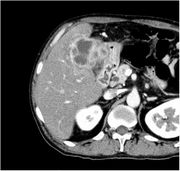

[黄色肉芽腫胆嚢炎] 手術:胆嚢摘出術(結腸切除術併施)

血液検査にて炎症反応の上昇を認め、精査の結果、急性胆嚢炎と診断。胆嚢摘出術(結腸切除術併施)を施行した。病理結果は黄色肉芽腫胆嚢炎であった。

CT画像